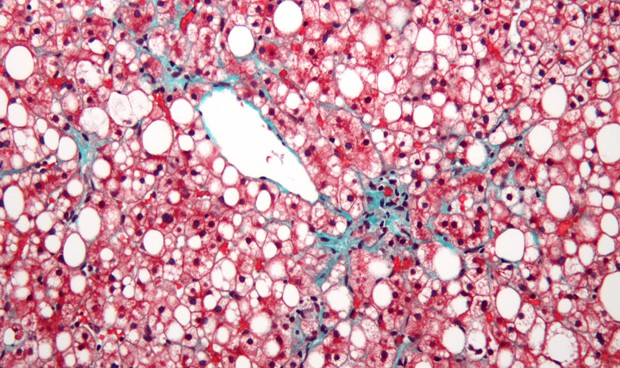

La esteatosis hepática no alcohólica es el subtipo inflamatorio de la enfermedad del hígado graso no alcohólico y se asocia con la progresión de la enfermedad, el desarrollo de cirrosis en el 20 por ciento de los casos y la necesidad de trasplante de hígado. Pero "a pesar de su importancia, no está reconocida en la práctica clínica", según una revisión publicada en JAMA

La esteatosis hepática está fuertemente asociada con la obesidad, la dislipidemia, la diabetes tipo 2 y el síndrome metabólico. Aunque existen varias pruebas no invasivas y sistemas de puntuación para caracterizar la enfermedad del hígado graso no alcohólico, la biopsia hepática es el único método aceptado para el diagnóstico según señalan los autores.